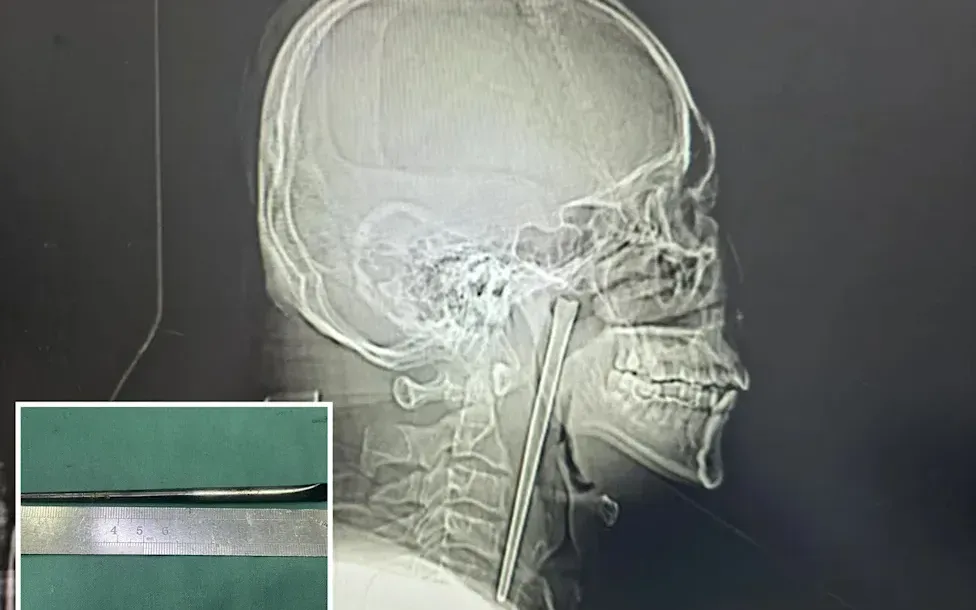

Ảnh chụp X-quang chiếc đũa dài khoảng 12 cm nằm trong cổ họng bệnh nhân. Ảnh: YouTube

Đáng chú ý, mặc dù dị vật tồn tại trong thời gian dài, dây thanh quản và niêm mạc xung quanh của bệnh nhân không bị tổn thương nghiêm trọng và vẫn hoạt động bình thường sau phẫu thuật.

Sau vài ngày theo dõi, bệnh nhân đã được xuất viện và được đánh giá có khả năng hồi phục hoàn toàn.